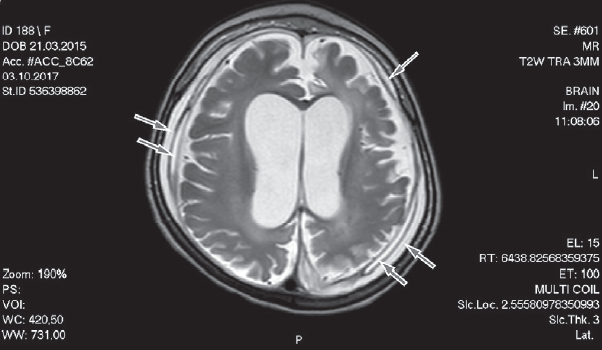

Субдуральная гематома — достаточно редкая, но серьезная патология головного мозга у детей грудного возраста, которая может привести к тяжелому неврологическому дефициту или закончиться летально. Субдуральные гематомы выявляются у 20–25 на 100 000 детей до 1 года. Ретроспективный анализ аутопсийного материала выявил, что у 72 % погибших детей в возрасте до 5 месяцев от внутричерепных кровоизлияний диагностированы субдуральные гематомы. По локализации субдуральные гематомы делятся на супра- и субтенториальные, преимущественно выявляются сочетанной локализации, которые лоцируются вдоль намета мозжечка и серпа головного мозга. Основной механизм развития субдуральных гематом связан с разрывом мостовых вен субдурального пространства в результате их натяжения, как травматической этиологии, так и возникающих при нетравматических повреждениях головного мозга, сопровождающихся прогрессирующей церебральной атрофией. Полагают, что одним из ведущих этиологических факторов развившихся субдуральных гематом у детей раннего возраста является перинатальное гипоксически-ишемическое повреждение головного мозга. Кроме того, формирование субдуральных гематом у детей раннего возраста может наблюдаться при внутриамниотических инфекциях, врожденных ферментопатиях и прежде всего у детей с ацидоуриями. У некоторых детей грудного возраста субдуральные гематомы протекают без клинической манифестации, но в большинстве случаев сопровождаются развитием неврологических нарушений, как в острый, так и в отдаленный периоды. В основном субдуральные гематомы в остром периоде манифестируют фокальными судорогами с вторичной генерализацией приступов, нарушением поведения, дыхания, симптомами внутричерепной гипертензии. При формировании хронической субдуральной гематомы наблюдается развитие структурной эпилепсии (до 20 %), микроцефалии, нарушение психомоторного развития. У 55 % детей раннего возраста с острыми субдуральными гематомами наблюдается формирование хронических субдуральных гематом.